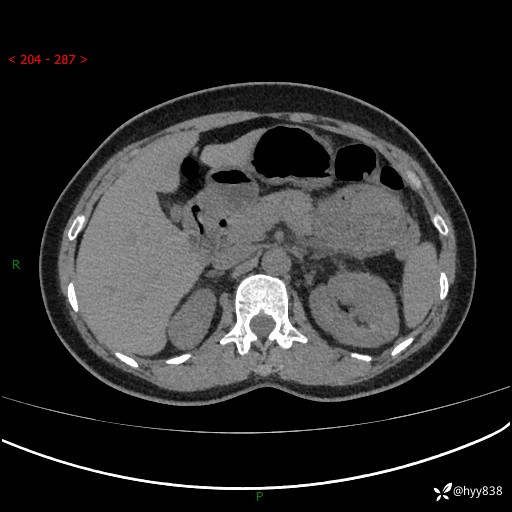

上腹部CT平扫